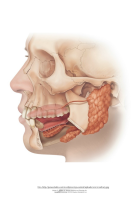

Samuti õpitakse tundma hamba ehitust ning selgitatakse piima- ja jäävhammaste ning sülje tähtsust.